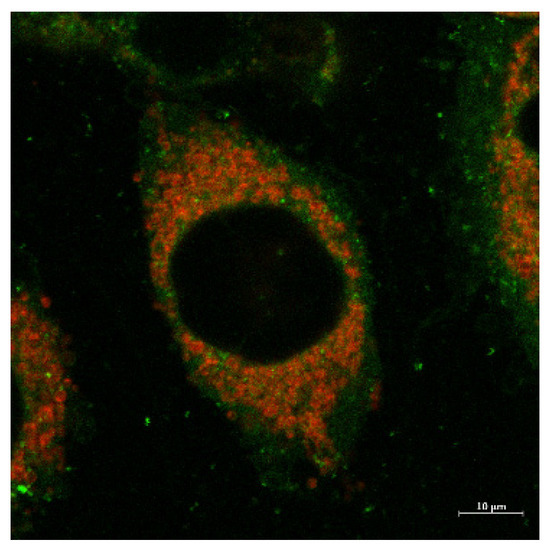

2.4. Fluorescent Imaging Study

Fluorescent Microscopy